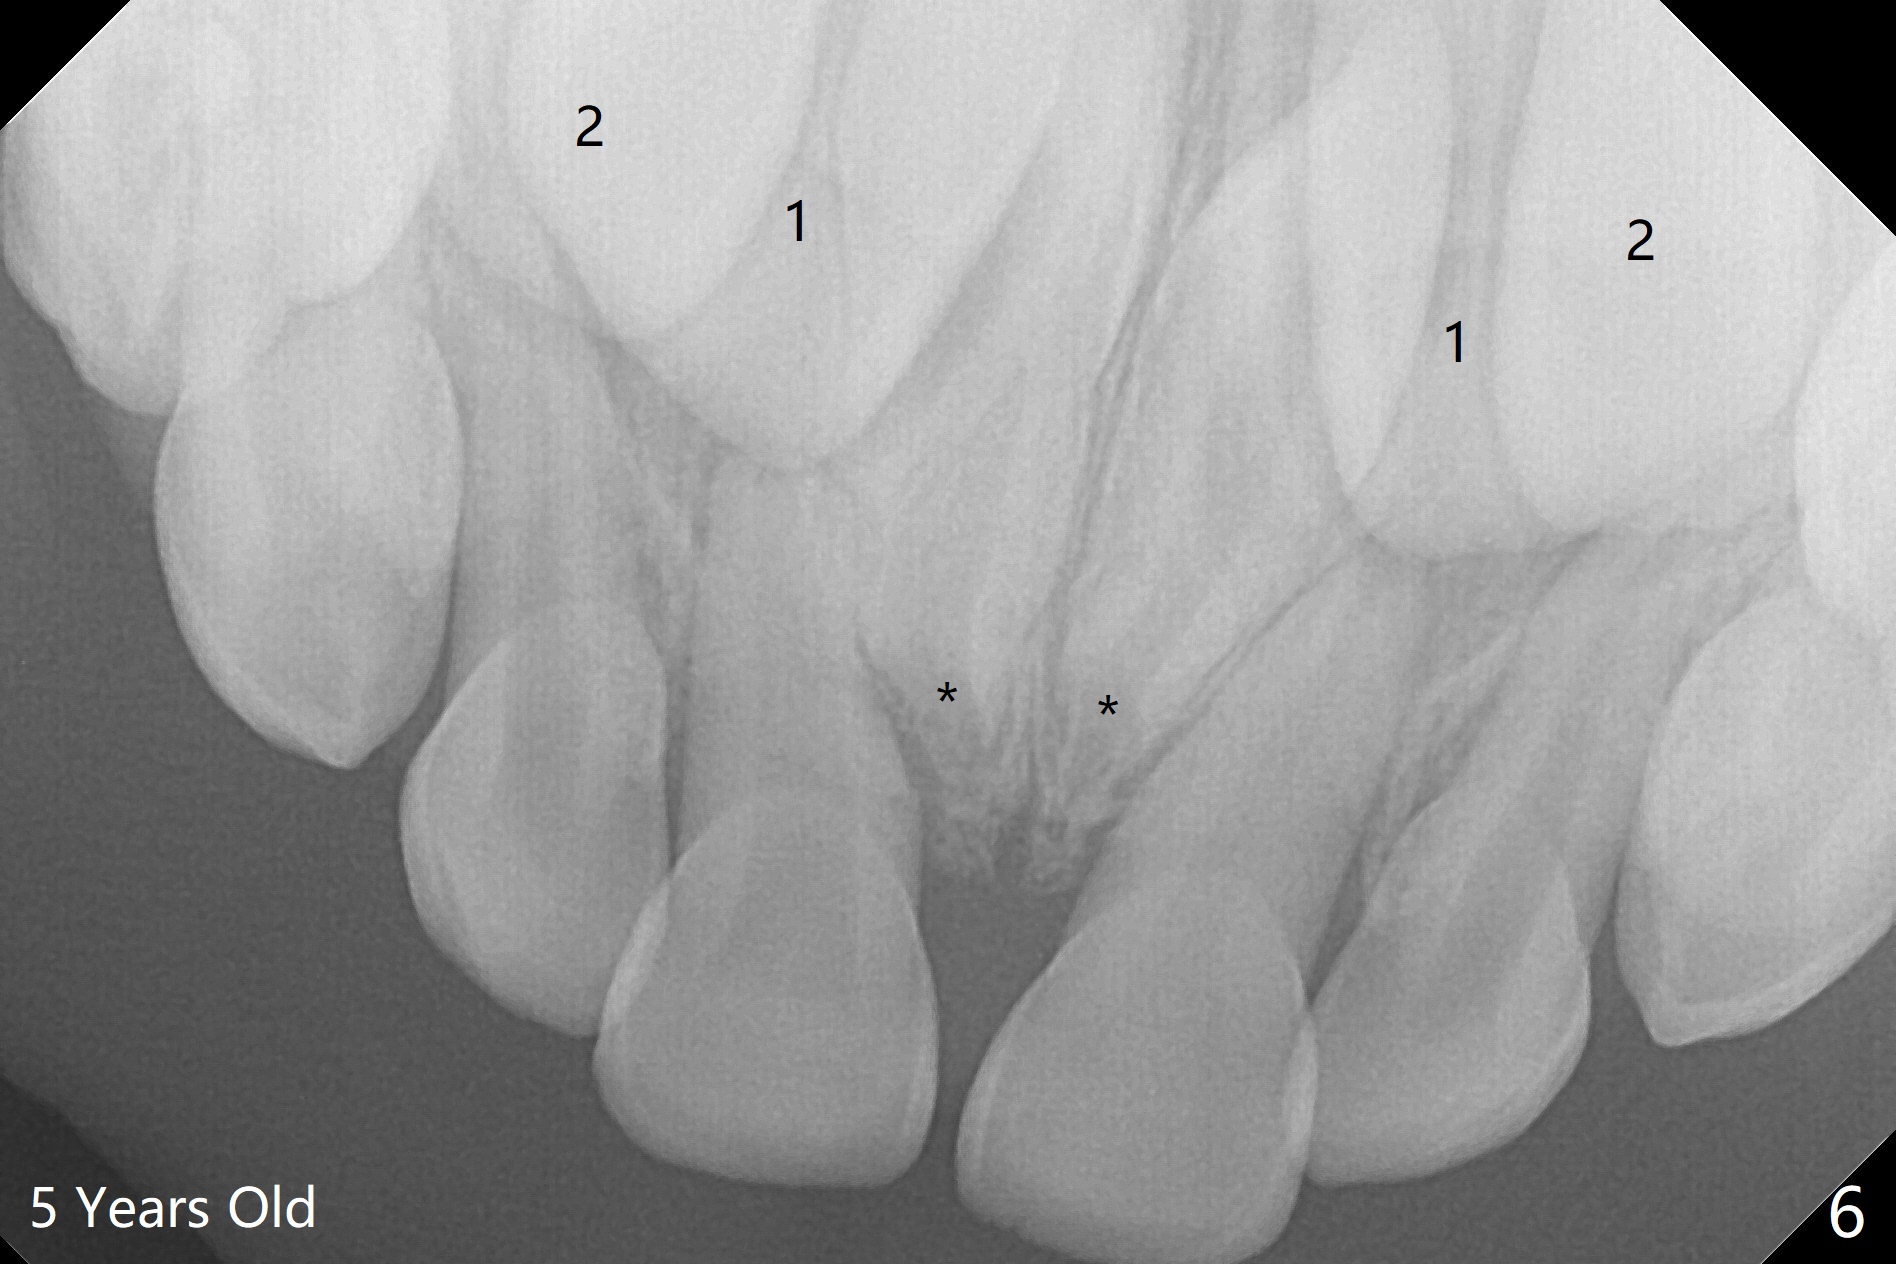

Figure 3 from The Effect of Early Removal of Mesiodens for the Dental Code For Extraction Of Mesiodens A mesiodens is an extra tooth that’s located behind or between your two front teeth. It’s typically identified during early childhood around the time that adult teeth are beginning to come in. Mesiodens tooth removal is a common procedure that involves the extraction of supernumerary teeth in the upper central. Some authors recommend extraction of mesiodens in the early mixed. Dental Code For Extraction Of Mesiodens.